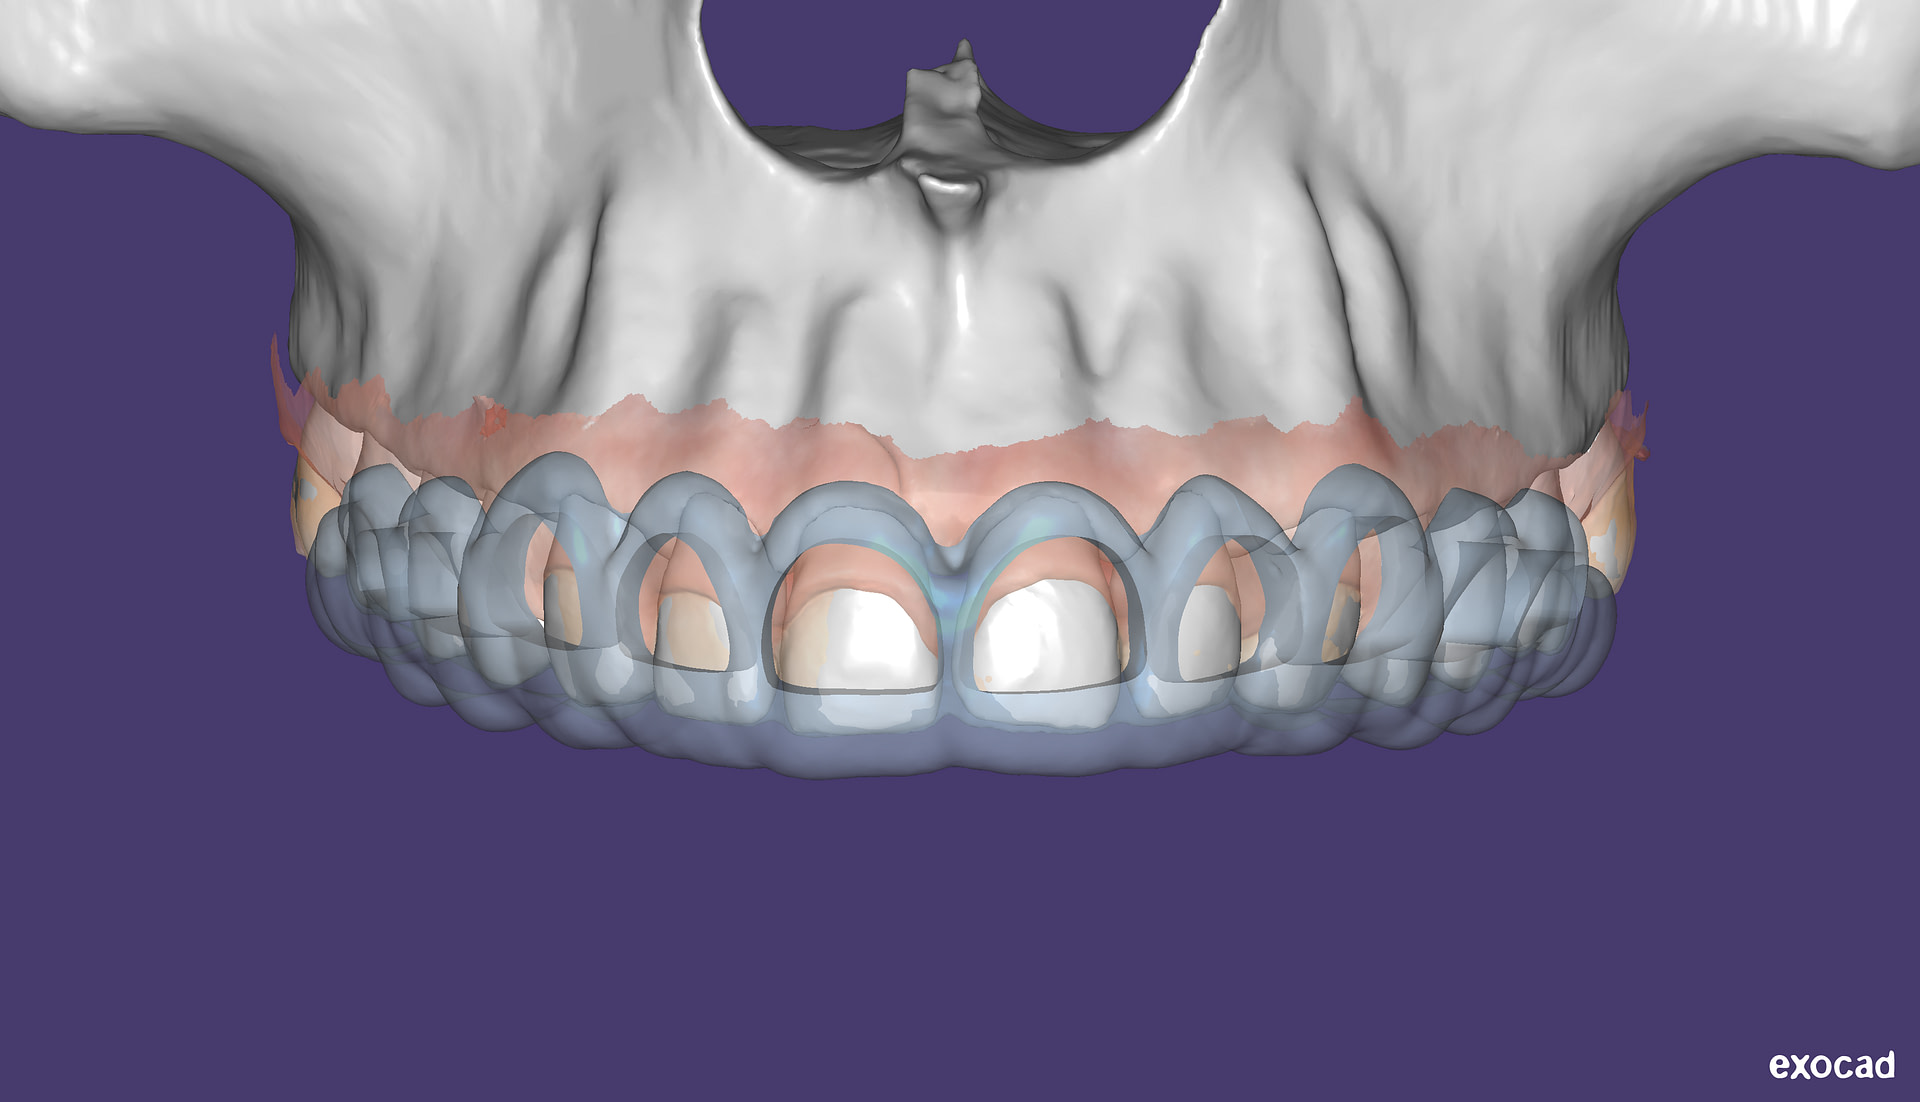

This is one feature that actually made Diagnocat very popular early on. It was the only software that made CBCT segmentation easy. Nowadays, there are several different companies and software that carry out segmentation. Diagnocat was the first and is still arguably the best at it.

So what is Segmentation? It basically means taking the CBCT and delineating all the different 3D structures, bones, individual teeth, etc.

These can then be individually exported via the software by generating STL files from CBCT dicom data. This can be used in other dental software. Jaw STLs can be used in Modjaw (jaw motion capture) for TMJ analysis, for example. As well as in exocad to help visualize the jaws for surgical planning or guide creation.

- CBCT segmentation

STLs of upper and lower jaws imported into Modjaw for TMJ analysis in jaw motion. this is made possible by CBCT segmentation using Diagnocat.

The surgical crown lengthening guide was made with the aid of maxilla STL to visualize crestal bone level. Again thanks to CBCT segmentation by Diagnocat.

CBCT Segmentation into STL

Generate STL files from CBCT DICOM data.

Generate maxilla and mandible in one STL file or face, teeth, maxilla, mandible, airway, cranial base, canals as separate STL files.